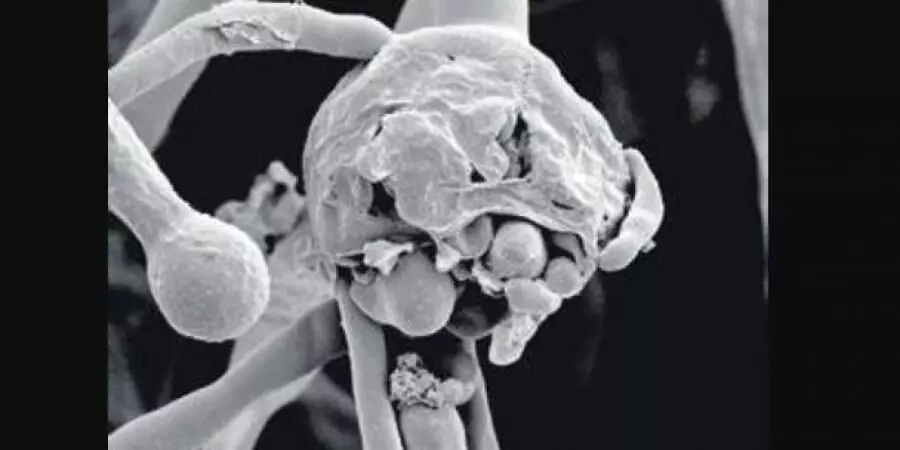

മലപ്പുറം: മഞ്ചേരി മെഡിക്കല്‍ കോളജില്‍ ചികിത്സയിലായിരുന്ന വീട്ടമ്മ ബ്ലാക്ക് ഫംഗസ് ബാധിച്ച് മരിച്ചു. പാലക്കാട് കൊട്ടശ്ശേരി സ്വദേശി വസന്ത (50) ആണ് മരിച്ചത് . ഇവര്‍ കൊവിഡ് ബാധിച്ച് ചികിത്സയിലായിരുന്നു. ഇന്നലെ കോവിഡ് നെഗറ്റീവ് ആയി. അതോടൊപ്പമാണ് ബ്ലാക്ക് ഫംഗസ് സ്ഥിരീകരിച്ചത് . നേരത്തെ പ്രമേഹത്തിനു ചികിത്സയിലായിരുന്നു.